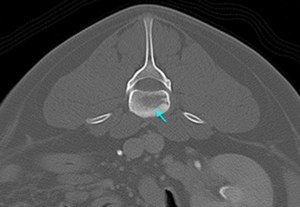

CT検査を実施してみると病変部は感染により、背骨が溶けていることも確認できた(水色矢印)

背骨の炎症が進み、骨が溶けてしまったと考えられる。